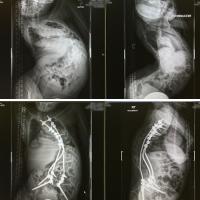

Post-operative x-rays (below) show how spinal instrumentation and fusion was used to correct the extreme curvatures present before surgery (above). The before and after images on the left show Noelle's spine from the front, and while the images on the right show her spine from a side view.

Dr. Roye performed a successful 10-hour spinal fusion surgery that helped to straighten and stabilize Noelle’s spine. After the surgery, Noelle says “day by day things got easier from a physical standpoint, and for the first time, I saw how long my torso was, which was almost six inches longer! It was just amazing and surreal.”